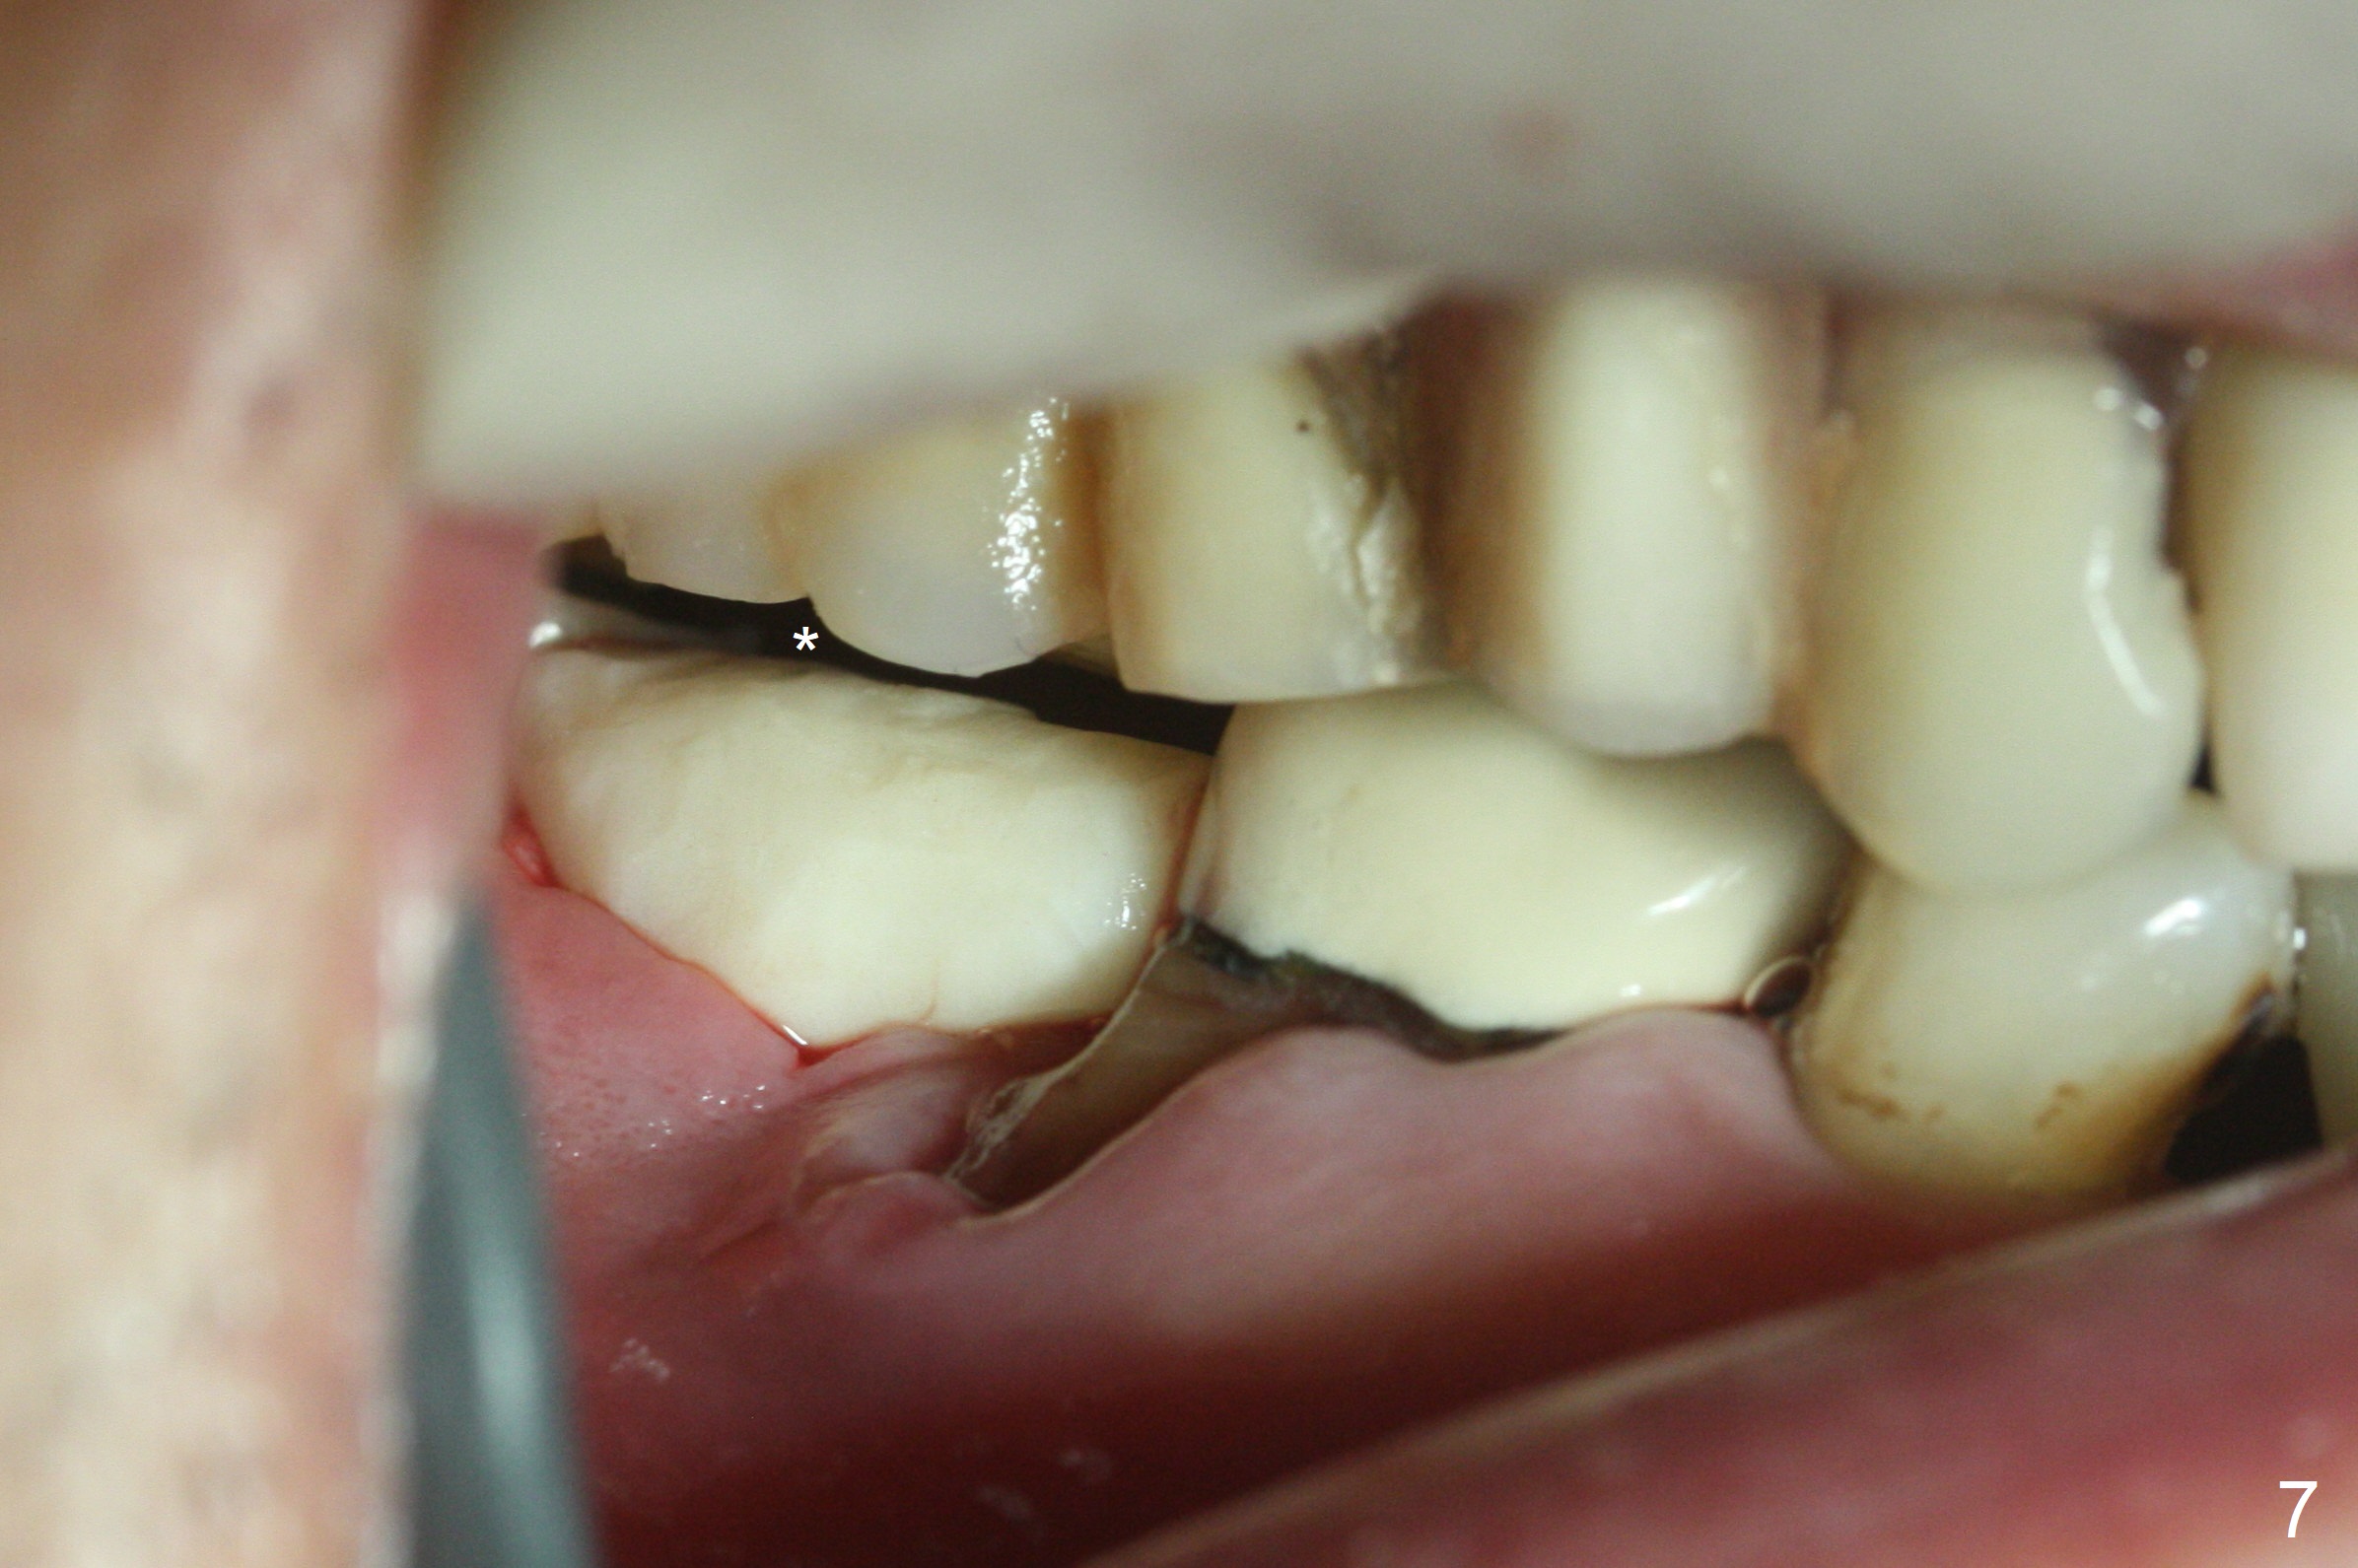

Although the tooth #30 has distobuccal root exposure (Fig.1 <), it is asymptomatic.  In contrast the tooth #31 with the distoocclusal caries (*) is symptomatic.  After use of 2 mm drill for 18 mm (lingual gingival margin), a calculated parallel pin is inserted (Fig.2 (D: 2 distal roots of the tooth #30)).  It appears that a 11.5 mm long implant is appropriate for the site; a 5 mm cuff is expected.  Following 4.8 mm drill, a 5.5x11.5 mm implant is placed initially (Fig.3) with an apical space (*) and clearance from the Inferior Alveolar Canal (red dashed line).  The implant is placed deeper with placement of a 6.5x4(5) mm abutment and bone graft (*, Fig.4,5).  After placement of collagen membrane over the graft, an immediate provisional is fabricated (Fig.6 P) with clearance from the opposing tooth (Fig.7 *).  There is no bone loss 3.5 months postop (Fig.8).  In fact the abutment has not been seated completely since its placement (Fig.4,5,8).  The crown/abutment dislodges 3 years 3 months post cementation (Fig.9).  The latter occurs for long incubation time because of opposing partial denture (Fig.10).  After trimming proximal surfaces (Fig.11: arrowheads), the abutment remains incompletely seated (Fig.11) due to possible crestal bone interference (Fig.11 *).  The smaller abutment by itself remains unseated (Fgi.12).  One size small one is completely seated (Fig.13).  Impression is taken.  Two weeks later the abutment margin is supragingival.  After screw torque at 20 Ncm, the crown is cemented with access hole.  Excess cement is removed.